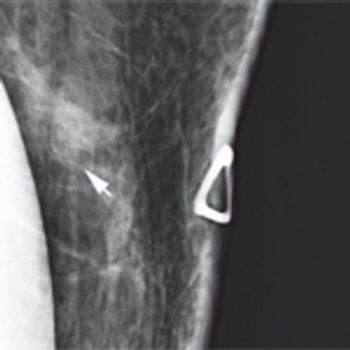

A 46-year-old woman had a routine screening mammogram that showed new calcifications in the posterior left breast. A diagnostic mammogram showed several small punctate calcifications, and a 6-month interval follow-up was recommended.